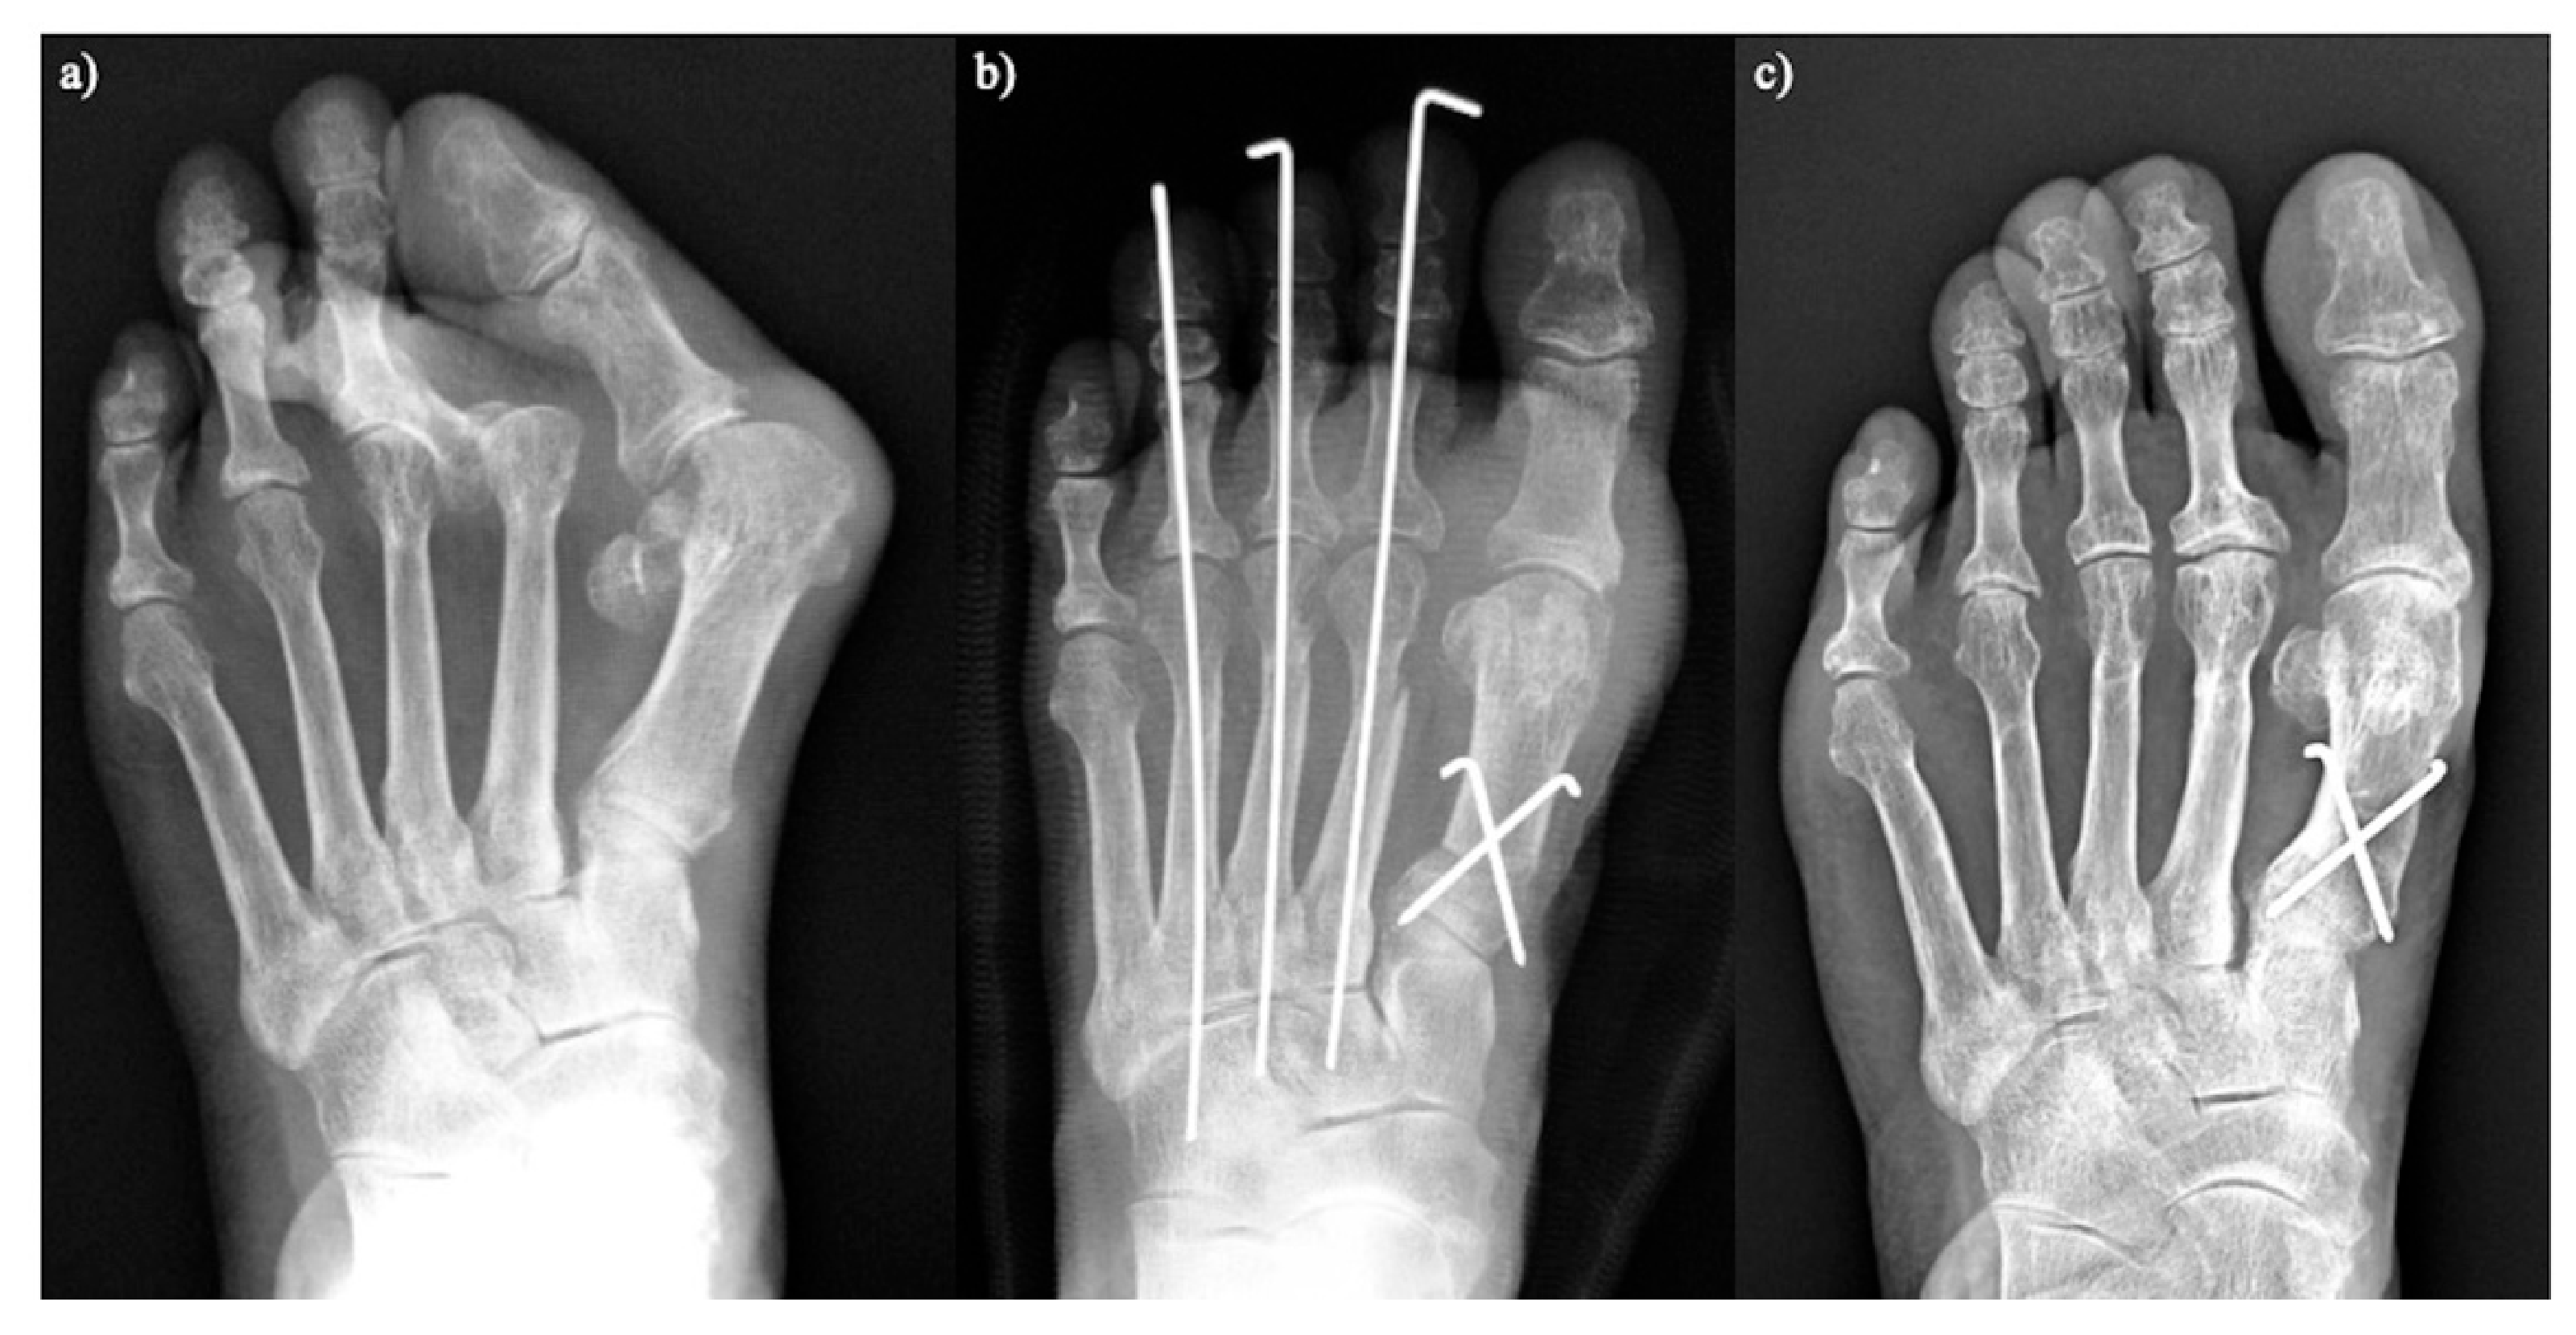

We assessed the long-term outcomes, including patient-reported outcome measures and radiographic evaluations, of proximal rotational closing-wedge osteotomy in 105 rheumatoid feet with a minimum follow-up of 5 years. Patient-reported outcome measures were evaluated using the self-administered foot evaluation questionnaire (SAFE-Q). All SAFE-Q subscales and radiographic values improved significantly over an average follow-up of 6 years. Recurrence of HV occurred in 10.5% of cases. The estimated survivorship of joint-preserving surgery with proximal rotational closing-wedge osteotomy of the first metatarsal and shortening oblique osteotomies of the lesser toes, at 7 years, with reoperation as the endpoint, was 89.5% (Figure 5) [20].

Figure 5. Proximal rotational closing-wedge osteotomy. (a) Preoperative. (b) Two weeks after surgery. (c) Five years after surgery.